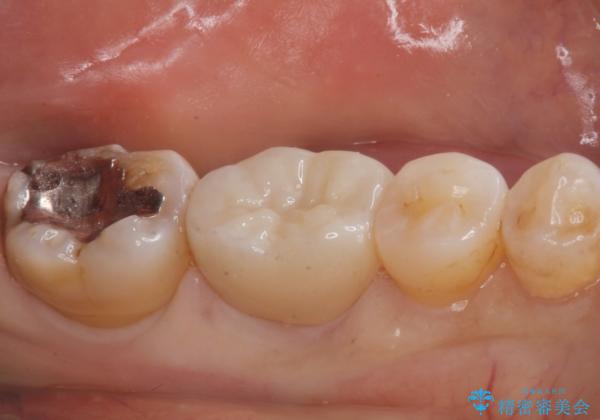

- 奥歯の銀の詰め物が取れたとの事で来院。

詰め物の下に虫歯ができて銀歯が取れてしまった事が予想されます。

白い詰め物でやり直しをしても歯質が薄くなり割れてしまうリスクがあるために、

割れるリスクの少ないジルコニアクラウンにて治療しました。